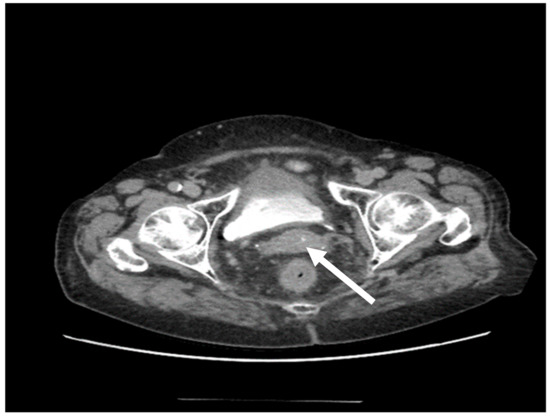

| 11. Weiyan Zhou [18] | 2016 | 1/31 | − | (DLBCL) | 6 × R-CHOP | 12 months/PET-CT/MRI |